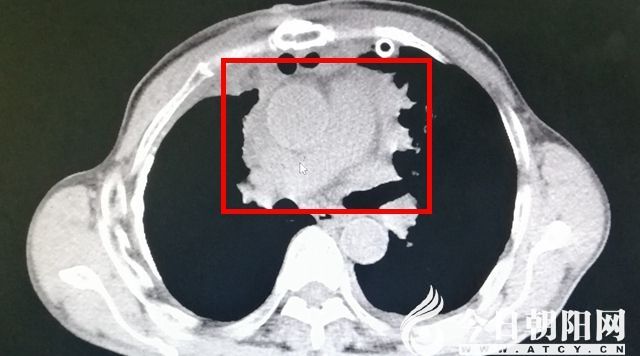

術(shù)前影像

患者李某(化名),因“呼吸費(fèi)力伴咳嗽2個(gè)月”到市二院就診?;颊呖谑?個(gè)月前無(wú)誘因出現(xiàn)呼吸費(fèi)力,活動(dòng)后明顯加重,就診于當(dāng)?shù)蒯t(yī)院,行對(duì)癥治療無(wú)明顯好轉(zhuǎn)。曾于赤峰某醫(yī)院行增強(qiáng)胸部CT檢查,提示為前縱隔囊實(shí)性占位,考慮惡性病變可能性大,因侵及心包、大血管,無(wú)法手術(shù),建議穿刺活檢保守治療。